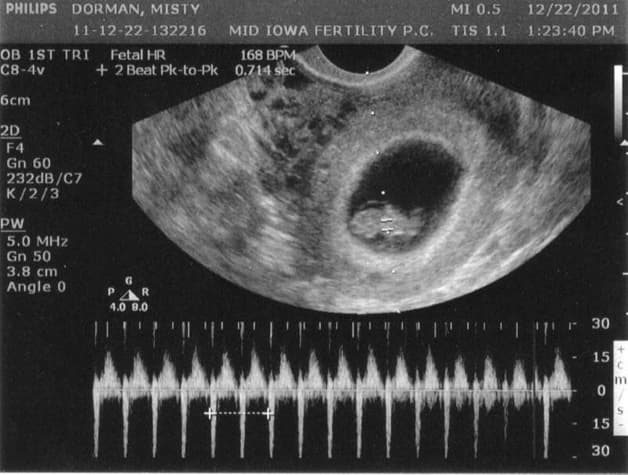

Từ những năm 1950, ngành y đã có thuật ngữ siêu âm thai. Siêu âm thai là bác sĩ dùng những máy quét siêu âm để nhìn thấy hình ảnh của thai nhi và tìm được những chỉ số quan trọng. Bác sĩ có thể chụp lại hình ảnh hoặc bố mẹ có thể xem hình ảnh trực tiếp trên màn hình siêu âm. Tuy nhiên không phải ai cũng có khả năng nhìn hiểu được những hình ảnh trên màn hình, nhất là với siêu âm 2D.

Sau khi siêu âm xong, các bác sĩ sẽ cung cấp những chỉ số và thông tin sau khi siêu âm được. Những chỉ số này là: đường kính lưỡng đỉnh, chiều dài đầu mông, đường kính túi thai, chi vi vòng đầu, số cân nặng ước lượng…

– FHR (Fetal Heart Rate): nhịp tim thai của thai nhi